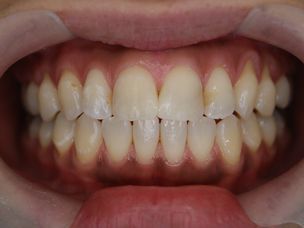

症例3

フィステル(瘻孔)があって、変色している症例。根管治療をすると、フィステルは消失。

で、漂泊してCR充填すればきれいに出来上がり。